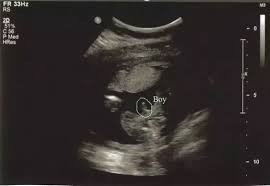

These baby gender tests deliver almost 99% accurate results. An ultrasound is one of the early methods for predicting a fetus's sex. One of the most common ways to do this is with an ultrasound, most frequently performed at between 18 and 20 weeks of gestation. This will be performed between 18 and 20 weeks. As these sound waves are released, they bounce off of internal surfaces and an image is generated on a computer monitor. When you're looking at 50/50 odds, predictions are bound to come true half the time. We're not quite at the submit your order online and receive it within 30 minutes point. It's accurate and completely safe for the fetus. You will notice these after birth as well, during diaper changes. The gender of the baby is determined at conception, althoug. 15 noticeable baby boy symptoms during early pregnancy. Private parts nub pointing up less than 30 percent = girl. There is one folktale, however, that scientists have studied — and it has to do with whether fetal heart rate can predict gender.

How early you can tell the gender of your baby depends on the method of detection you use. And surprisingly, at least a couple of these methods do have some evidence to back them up. Ultrasounds are often more accurate because you can see body parts more clearly, as opposed to guessing from shadows. Conventional wisdom holds that if the baby's heart rate is less than 140 beats per minute you're having a boy and if it's more than 140 beats per minute you're having a girl. Private parts nub pointing up less than 30 percent = girl. These baby gender tests deliver almost 99% accurate results. Can you tell gender at 10 weeks? Healthcare providers can do this test toward the end of the first trimester, usually at about 10.

There is one folktale, however, that scientists have studied — and it has to do with whether fetal heart rate can predict gender. Healthcare providers can do this test toward the end of the first trimester, usually at about 10. The greater availability of 3d and 4d ultrasounds has changed how ultrasounds determine a baby's gender. But developments in noninvasive prenatal tests (nipts) mean you can be let in on this little secret with a. You will notice these after birth as well, during diaper changes. One of the most common ways to do this is with an ultrasound, most frequently performed at between 18 and 20 weeks of gestation. These baby gender tests deliver almost 99% accurate results. Clinically proven to be 99.9% accurate This test can be done at week 10 of your pregnancy and is 99% accurate. Known as one of old wives tales, the chinese gender calendar is a very ancient tool allowing you to find out if the baby you're conceiving is a boy or a girl. Private parts nub pointing up less than 30 percent = girl. Conventional wisdom holds that if the baby's heart rate is less than 140 beats per minute you're having a boy and if it's more than 140 beats per minute you're having a girl. That dark line that runs from your pubic bone straight up the center of your belly (known as the linea nigra) is said to indicate baby's sex.